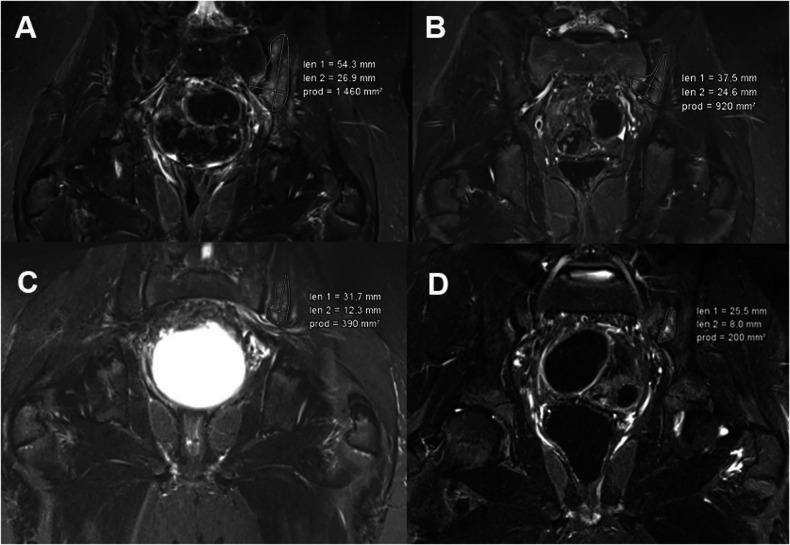

Methods: A retrospective analysis of MRI examinations was conducted on 29 children and adolescents with CNO. CNO lesions were segmented. Sarcopenia was assessed using the total psoas muscle index (PMI) at lumbar vertebral levels L3/4 and L4/5. Measurements were taken at four time points during the disease course (T1: baseline, T2-T4: follow-up). Based on the PMI, patients were classified as sarcopenic or non-sarcopenic, and the progression of CNO lesions and the impact of sarcopenia were analyzed.

Results: A total of 29 patients, aged 1-16 years, were included in the study, with 13 males and 16 females. Patients with sarcopenia had a significantly larger mean lesion area (868.95 mm2, SD = 684.49) compared to those without sarcopenia (636.11 mm2, SD = 832.41); p = 0.042, d = 0.4). The comparison between the two patient groups revealed a consistently lower percentage reduction in lesion size for the sarcopenic patients at all time points. Notably, the difference between T1 and T3 was statistically significant (p = 0.045, d = 0.82).